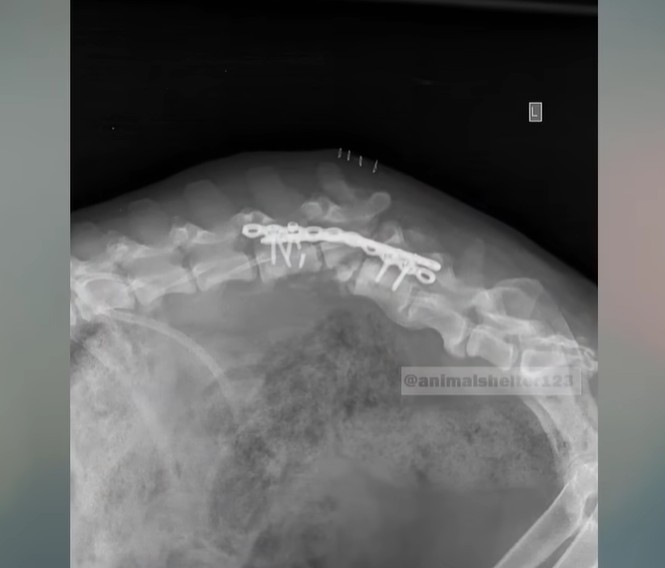

Then came the X-rays, revealing a devastating reality.

Indra’s spine was broken completely in half. It was the absolute worst injury the attending veterinarian had ever seen. The fact that she had dragged herself to the road with a shattered spine just to get help for her puppies was nothing short of miraculous. While her four babies were placed under heat lamps and carefully fed, Indra had to prepare for a grueling medical journey.